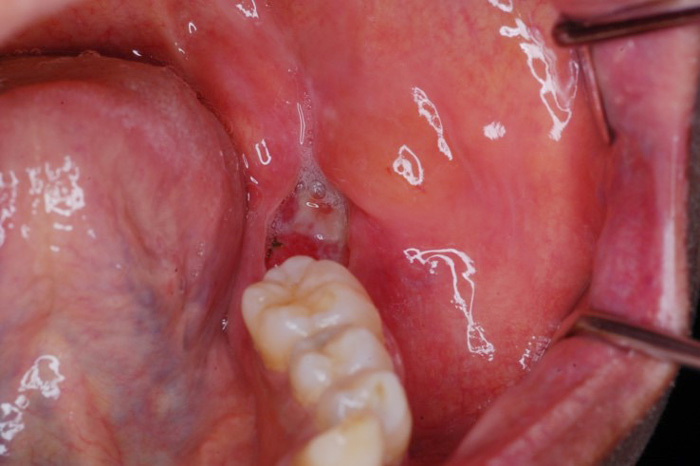

代表画像(下顎歯肉癌)

下顎歯肉癌

治療後(金属プレート再建+前腕皮弁再建)